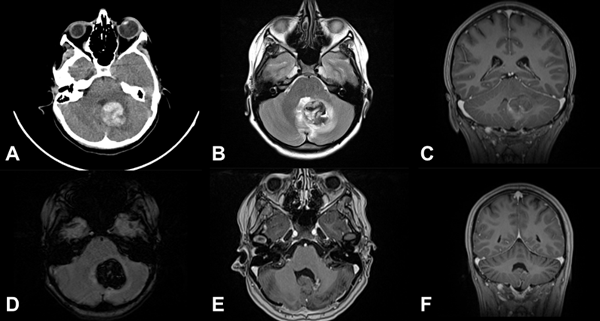

Figura 5. MC cerebral infratentorial cerebelosa. Paciente femenino de 15 años, consulta por síndrome cerebeloso. A) TC de cerebro que muestra imagen espontáneamente hiperdensa en región vermiana y pedúnculo cerebeloso medio izquierdo. B) RM secuencia T2 que muestra lesión heterogénea con edema perilesional. C) RM secuencia T1 con contraste EV en plano coronal que muestra la relación de la MC con el receso superolateral. D) RM-SWI que muestra lesión con componentes hemáticos. E-F) RM postquirúrgica cerebral, secuencia T1 con contraste EV, se muestra resección completa de la malformación cavernosa.

Figura 6. MC medular a nivel T10. Paciente masculino de 15 años que ingresa por paraplejía progresiva de varios días de evolución y compromiso de esfínteres. A) RM de columna dorsolumbar corte sagital T2-STIR que evidencia lesión heterogénea, compatible con MC. B) RM corte axial T2-STIR. C-D) RM de cerebro secuencias SWI y T2 que muestra otra lesión en hemisferio cerebeloso derecho. Por la severidad del cuadro clínico se realizó cirugía de urgencia. E-F) RM de columna dorsolumbar postquirúrgica, secuencias T1 y T2-STIR donde se observa el lecho quirúrgico libre de lesión. Se observa laminectomía del nivel T10. El paciente tuvo una recuperación parcial del foco neurológico. Actualmente en rehabilitación.